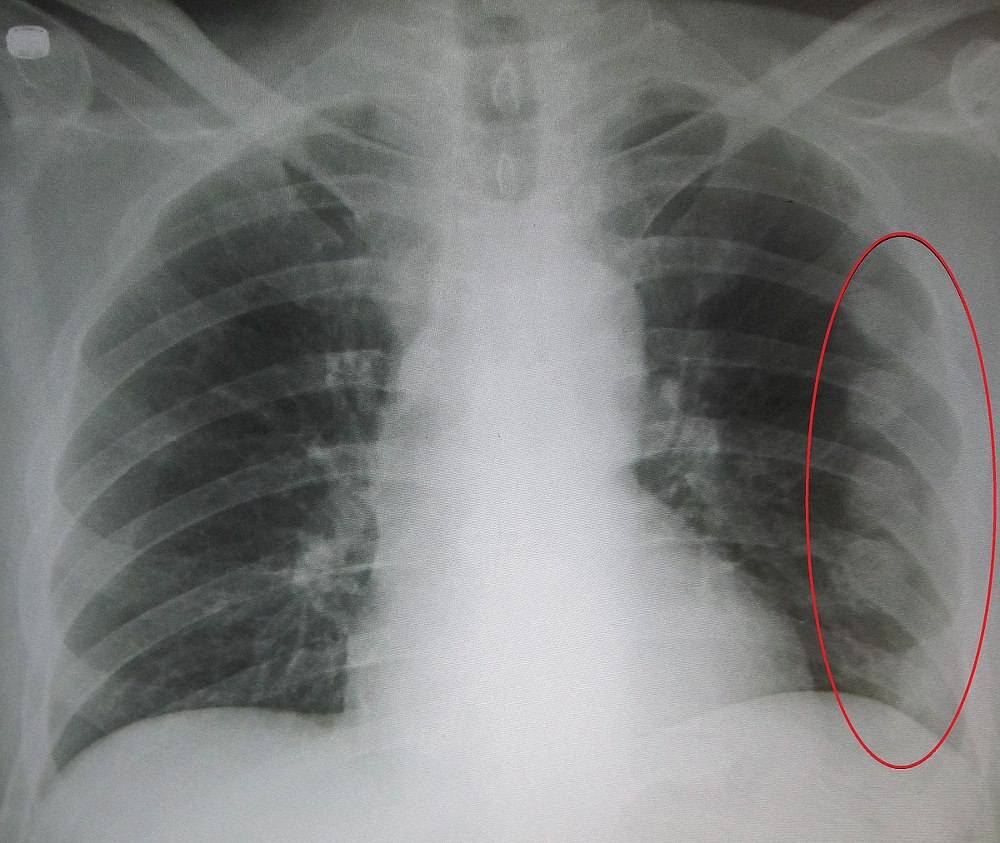

갈비뼈는 우리 몸의 중요한 부위 중 하나로, 흉곽과 연결되어 있으며 폐와 심장을 보호하는 역할을 합니다. 갈비뼈가 금이 가는 상황은 스포츠 활동이나 일상 생활에서 발생할 수 있으며, 이로 인해 심한 통증과 불편함을 경험할 수 있습니다. 이 글은 갈비뼈에 금이 가면 나타나는 증상과 치료 방법에 대해 알아보겠습니다.

- 심한 통증: 갈비뼈 금이가 발생하면 갈비뼈 부분 전체적인 통증이 나타납니다. 특히 갈비뼈가 움직이거나 주변 근육이 움직일 때 통증이 더욱 심해집니다. 숨을 쉴 때도 통증을 느낄 수 있어 숨쉬기가 불편할 정도입니다.

- 동작 제한: 갈비뼈 금이로 인해 갈비뼈가 어긋나게 틀어지는 경우는 드뭅니다. 그러나 갈비뼈 금이가 나타나면 흉부와 상체 움직임에 제한이 생깁니다. 윗몸 일으키기나 힘을 가하는 운동을 하면 극심한 통증이 발생하여 해당 동작을 수행하기 어려울 수 있습니다.

- 통증 강도: 갈비뼈 금이는 선상 골절이라도 갈비뼈 부분 전체적인 통증으로 나타나기 때문에 인지되는 통증의 강도는 실제보다 더 괴로울 수 있습니다.